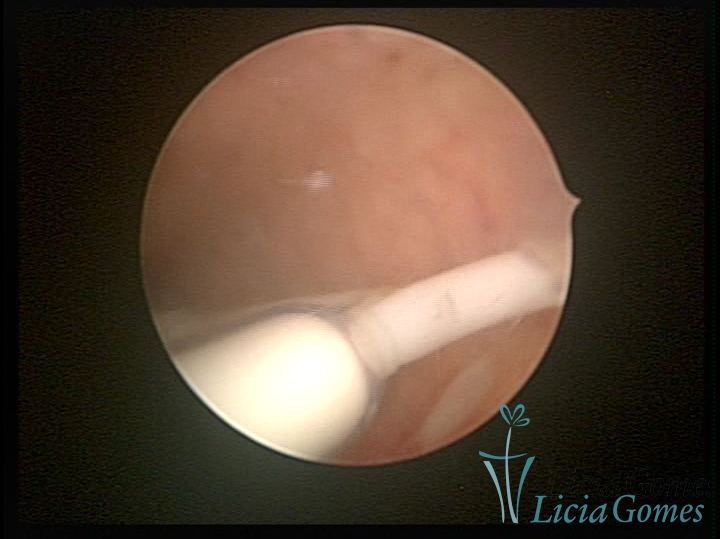

Cervical canal with IUD string